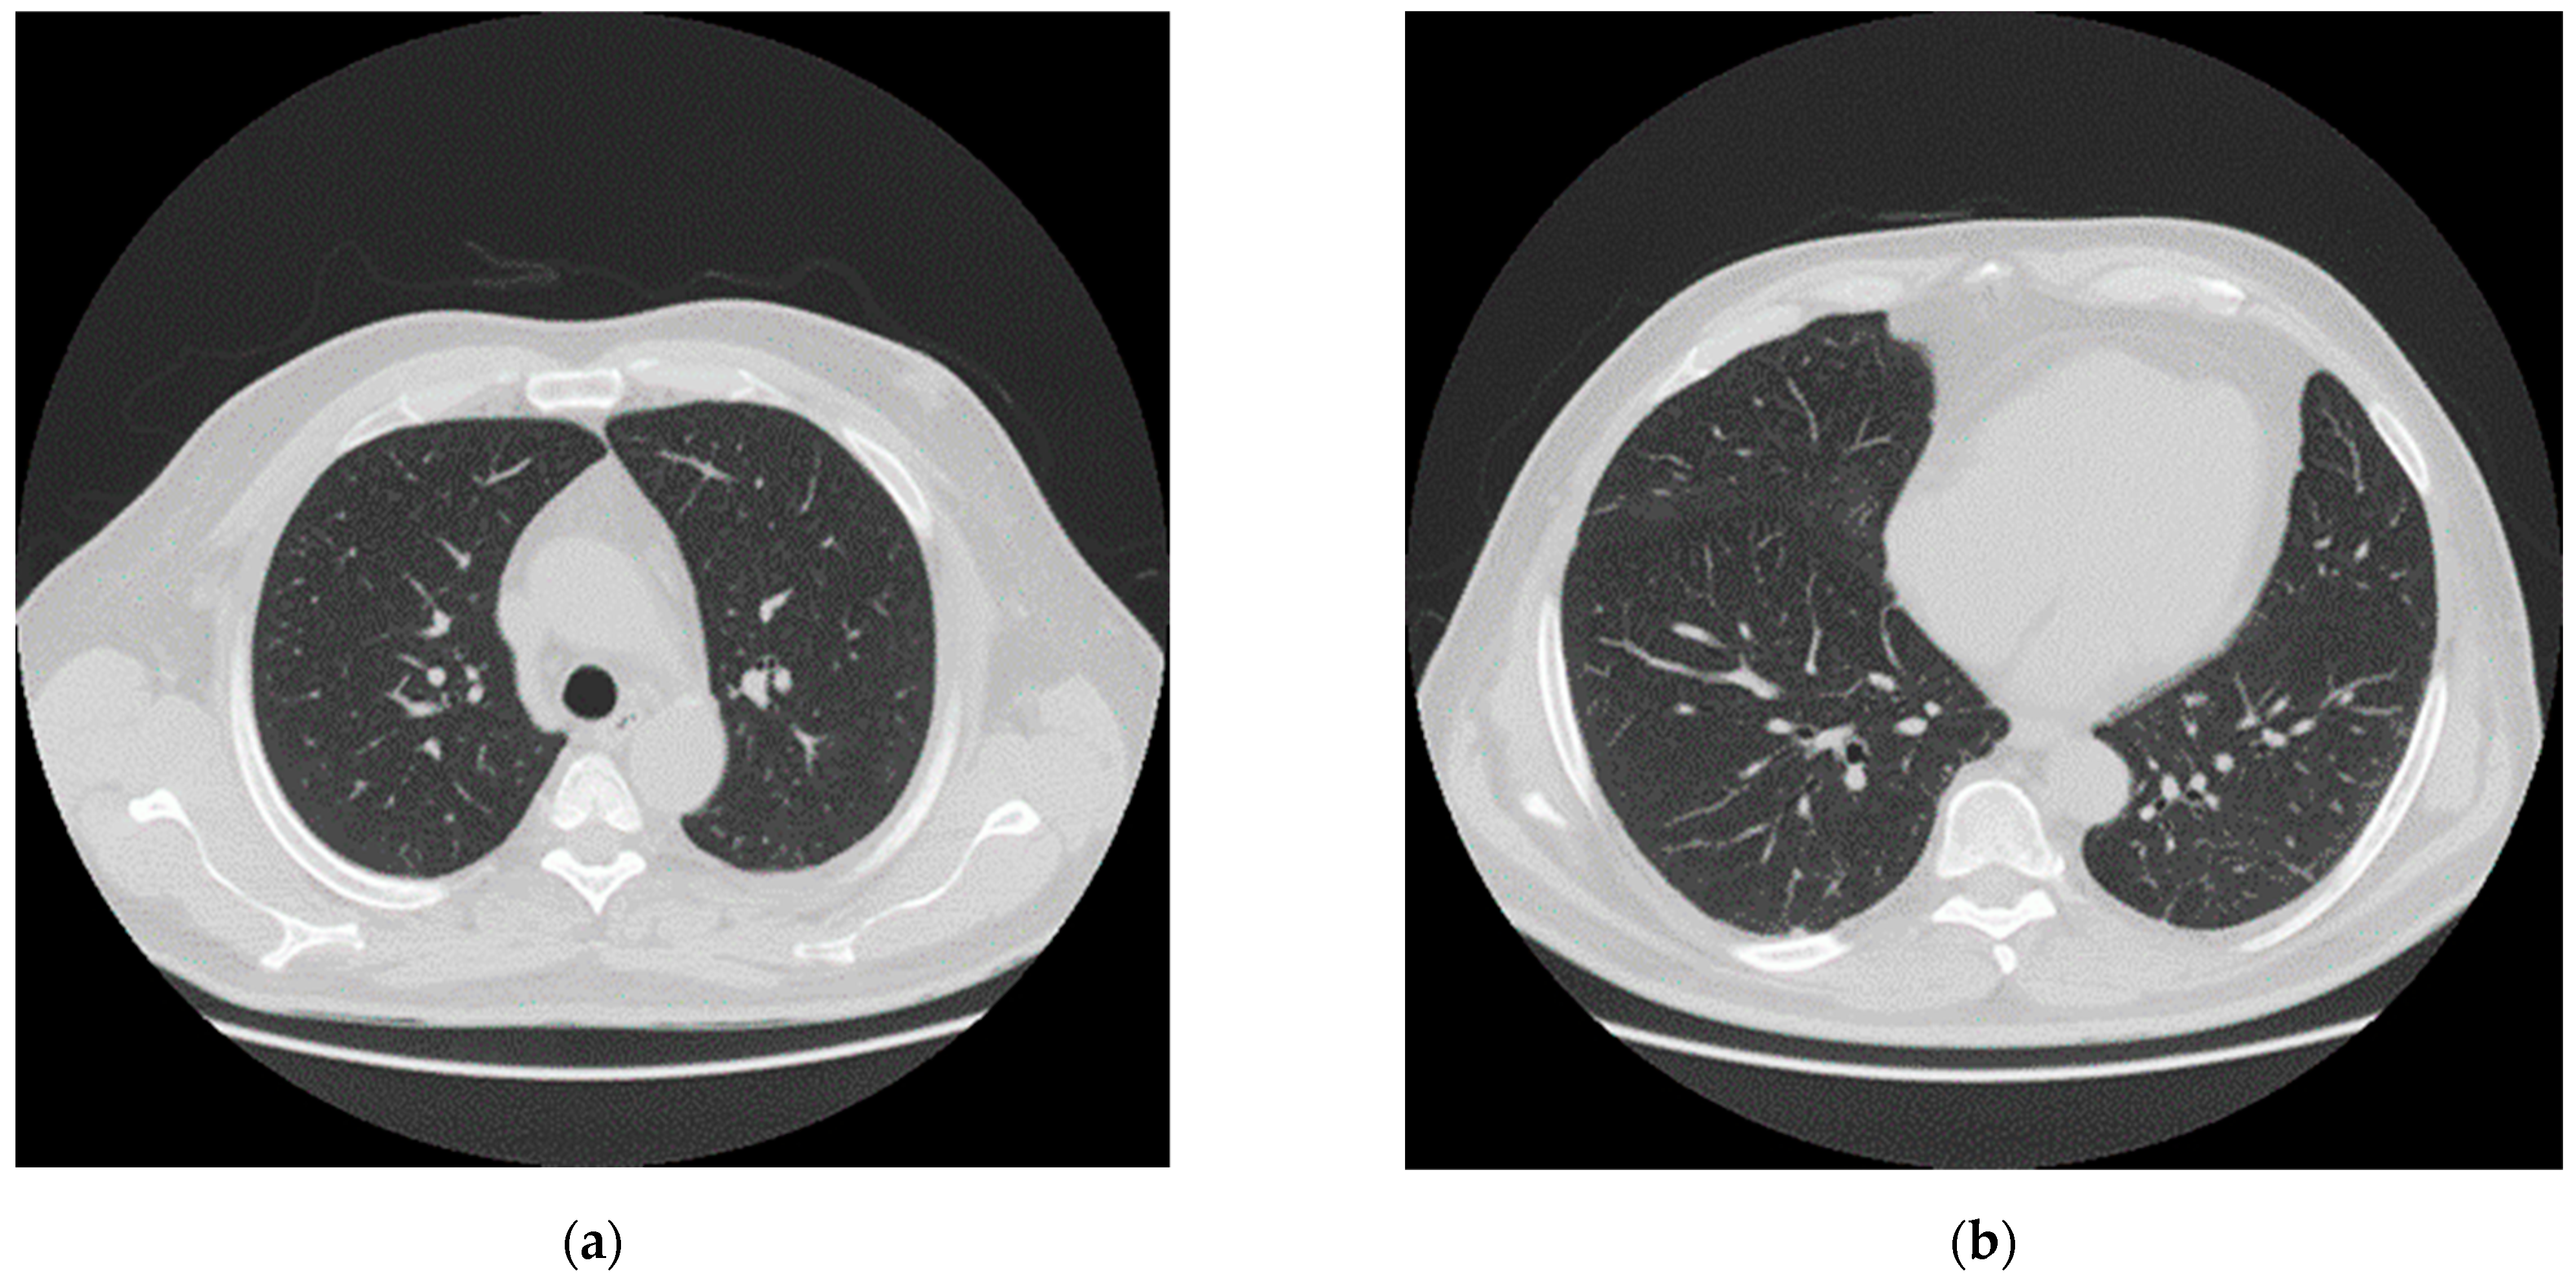

After one month of intensive care (April 2020), the patient was transferred to sub intensive care, due to the improvement of the respiratory functions. The neurological examination indicated that the patient showed difficulty walking, weakness in the lower limbs, lack of strength in the pelvic girdle muscles and skin hyperalgesia especially in the backside. Chest CT showed almost complete resolution of the pulmonary damage (Figure 3). In May, SARS-CoV-2 reverse transcription PCR test and antibody test were negative.

Figure 3.

CT after one month of intensive care and one month of sub intensive care. (a,b) Axial nonenhanced chest CT images (lung window) show almost complete absorbent of lesions.